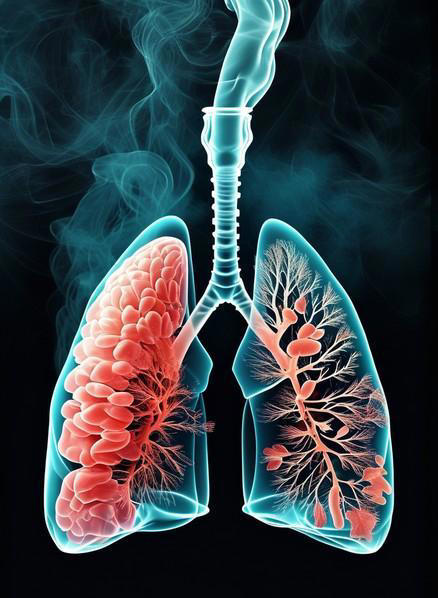

肺结节这个词现在出现频率挺高的,但它本身只是一个影像学描述,意思是肺里出现了一个圆形或类圆形的密度增高影,不等于就是癌。

结节分很多种,磨玻璃样结节、混合密度结节、纯实性结节,三者的处理逻辑和风险程度差别很大,不能一刀切地看待。

医生真正担心的,是实性结节,而且是直径达到8毫米或以上的。为什么8毫米是个分水岭?有数据支撑的。

国内外多项肺结节随访研究的数据均显示,直径不足6毫米的实性肺结节,恶性概率低于1%,几乎可以按年度随访观察。

直径在6到8毫米之间的,恶性率上升到约1.5%至6%;而一旦超过8毫米,恶性率会跳升至15%到25%,部分高危人群的比例还会更高。《中国肺癌筛查与早诊早治指南》中也明确将8毫米实性结节列为需要积极干预的阈值。

报告里出现"实性成分增多"这几个字,同样不能轻视。这个描述暗示之前可能是磨玻璃结节,现在密度变高了、变实了,这种动态变化在影像学上是一个高度敏感的信号。

提示病灶很可能在进展。遇到这种情况,不建议自己观察等待,尽快找呼吸科或胸外科评估才是正确做法。

第二个:报告出现"毛刺征"、"分叶征"或"胸膜牵拉凹陷"

这几个词放在一起,专业上称为"形态学恶性征象",说的是结节长得不正常。良性结节通常边缘光滑、整齐,而恶性结节往往"不守规矩",边界不清、形状怪异。

毛刺征是指结节边缘向周围组织伸出细小的条索状影,这是肿瘤细胞向外浸润蔓延的一种影像学表现,不是普通炎症能做到的。

分叶征指结节的轮廓呈波浪状或分叶状,原因在于肿瘤在不同方向上的生长速度不一致,导致形状凹凸不平。

胸膜牵拉凹陷则说明结节和胸膜之间产生了牵连,局部胸膜被"拉"出了一个小坑,这通常意味着病灶对周围组织已经产生了一定程度的影响。

这三种征象单独出现时,恶性可能性已经升高;两种或三种同时出现,风险叠加明显。国内相关研究数据显示,同时具备毛刺征和分叶征的实性结节,恶性概率可超过60%。

不过有一点需要说清楚,CT征象只是影像学参考,恶性与否的最终定性,依然要靠病理结果,不能凭报告上几个词就给自己扣帽子,但也绝不能置之不理。